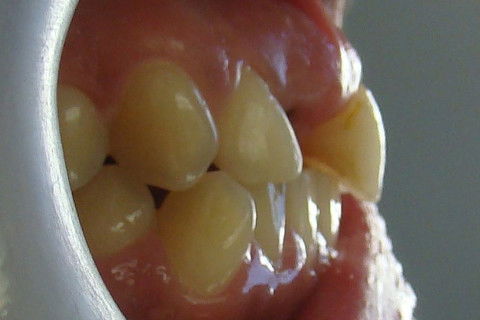

Retorno após 9 meses da colocação de coroa metalo-ceramica parafusada

Retorno após 9 meses da instalação de coroa metalo-ceramica parafusada

Paciente com implante feito em curso de atualização, chega ao consultório para reabertura e coroa metalo-ceramica unitária, com grande depressão gengival na vestibular do elemento 11. Feita a reabertura com concomitante enxerto de tecido conjuntivo para otimizar os tecidos moles, aguardamos 3 semanas para inicio das moldagens para a coroa temporária. Após colocação e ajustes da coroa temporária parafusada, aguardamos 3 meses para completa maturação dos tecidos e então fizemos nova moldagem, com personalização do transferente para moldeira aberta individual e fizemos coros metalo-cerâmica parafusada.